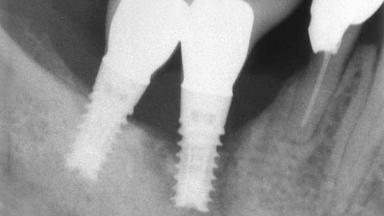

A 82-year-old female patient was referred to the Department of Oral Surgery and Stomatology at the University of Bern, Switzerland, for further diagnosis and treatment of growing discomfort in the right mandible (implant 45) and left maxilla (implant 23). The patient had had implants of various types inserted in the mandible and maxilla over the course of the previous three decades (in the 1980s and 1990s). The patient had received removable partial dentures on implants in the maxilla and on natural teeth in the mandible. The implants in the posterior right mandible had been restored with two splinted single crowns. The lower partial denture was not well tolerated by the patient and therefore had not been worn for over ten years. After insertion of the implants, there had been no complications for many years, but implants 45 and 46 as well as 23 had begun to exhibit signs of peri-implantitis with limited bone loss several years previously. The infection had been treated by the private practitioner, and bone loss around the three implants had not progressed until about half a year previously.